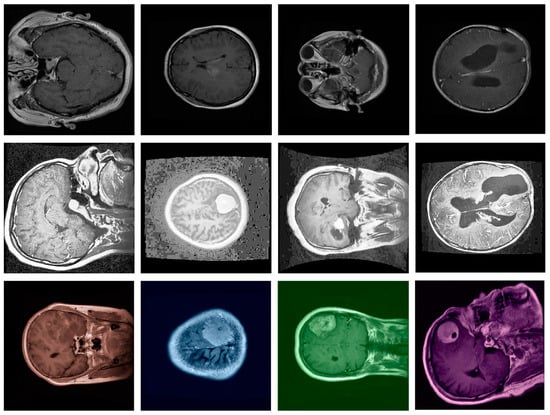

- Our model was evaluated on the Figshare dataset, which includes annotated MRI images of different brain tumor types: meningioma, glioma, and pituitary tumors. We provide a comprehensive comparison against leading segmentation models. Our results demonstrate that the proposed model achieves superior performance across metrics like accuracy, DSC, precision, and recall, confirming its robustness and reliability for clinical application.

- We introduce a preprocessing pipeline that includes normalization, resizing, histogram equalization, and data augmentation techniques. This pipeline, tailored for medical imaging, contributes to improved model generalization and robustness in segmentation performance, addressing common challenges in medical image analysis due to variations in imaging protocols.

4.1. The Dataset